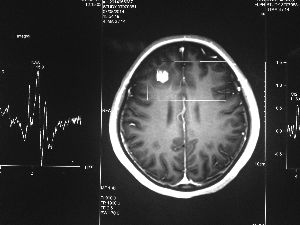

方框亮點為CT片顯示的異物

今年6月份,張敏在宿舍休息時,又發(fā)起了癲癇,也是口吐白沫,渾身抽搐。送到蘇州一家大醫(yī)院,頭顱核磁共振檢查出,張敏大腦右額葉處有一處病灶,也就是大腦額頭處有個東西。

腦袋里的東西,到底是腫瘤還是其他什么東西,這個謎像個石頭一樣,壓得張敏一家人喘不過氣。7月份,張敏一家又來到南京腦科醫(yī)院求醫(yī),第三次檢查后,醫(yī)生覺得很像是寄生蟲。不過,影像的檢查,只能作為醫(yī)生推測的依據,具體是什么,只有手術拿出來后才能知道。